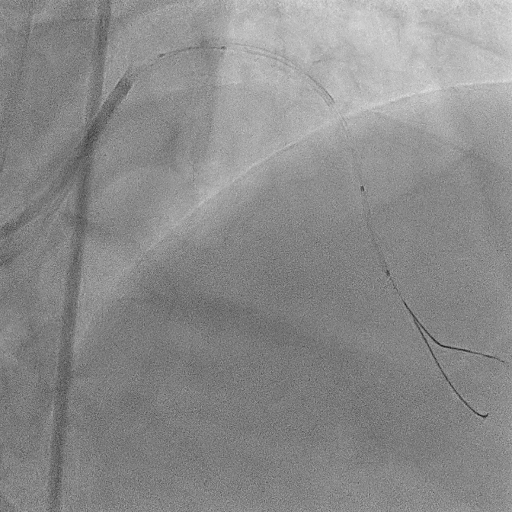

The procedure commenced with EBU 3.5/6F catheter and CTO wire with microcatheter. Managed to cross the lesion and changed to workhorse wire. Proximal LAD ISR predilated with SC balloon 2.0/15mm. CTO at mid segment predilated with same balloon. However, noted perforation at mid LAD after predilatation. We used the same balloon to tamponade the perforation and attempted to wire down distal LAD with another wire but failed. Right femoral puncture was performed and another EBU3.5/6F was used. The ping pong technique was used in which another workhorse wire to distal LAD when tamponade balloon was deflated. However, the covered stent was unable to cross the proximal LAD. Proximal segment was then predilated with NC 2.5/15mm, yet still unable to advance the covered stent. Subsequently, guide extension GuidePlus II was used and managed to advance covered stent 2.5/20mm. Tamponade balloon was then removed and covered stent deployed at perforation site. We proceeded with drug coated balloon angioplasty to proximal-mid LAD using DCB 3.5/20mm. Patient was stable and bedside echo revealed minimal pericardial effusion only